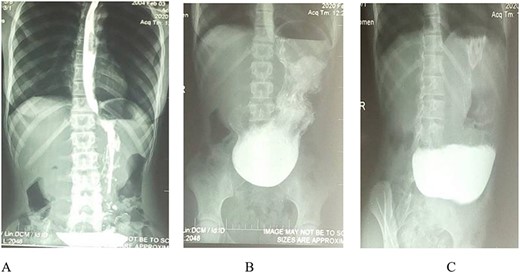

Barium meal: (A and B) Erect anteroposterior view show prolongation of stomach to suprapubic region. B and C (oblique view): Show gastric distension, no passage of contrast medium into the duodenum and delayed gastric emptying (C).

A 16-year-old girl was admitted to our hospital with abdominal pain, vomiting and moderate growth retardation. She was healthy and well-nourished until 12 years of age when she began having abdominal pain and projectile non-bilious vomiting, especially after heavy meals. During the two subsequent years, she gradually lost weight, with increasing frequency of vomiting after both heavy and light meals, even after drinking water, and now associated with constipation. She consulted a physician and a diagnosis of hypertrophic pyloric stenosis was made based on ultrasonography findings. She was then operated for hypertrophic pyloric stenosis. Six months later, she started experiencing the same symptoms with a similar pattern (gradual increase in frequency and intensity). She had a history of peptic ulcer disease since 11 years of age, but no history of caustic ingestion, malignancy, gastric polyps or non-steroid anti-inflammatory drug medication. There was a positive family history of peptic ulcer disease, but no family history of parental consanguinity. Physical examination revealed an afebrile and haemodynamically stable patient with anthropometric parameters between the 10th and the 5th percentiles. Her abdomen was not distended but showed an epigastric tenderness, and normal bowel sounds were heard on auscultation. However, visible gastric peristalsis was observed during bouts of vomiting. She was positive at the Helicobacter pylori serology and routine urine tests were normal, as well as serum electrolytes, renal and liver function tests. A barium meal showed marked gastric distension, with delayed gastric emptying and no contrast medium in the duodenum (Fig. 1). These findings were consistent with gastric outlet obstruction but of unknown aetiology. An exploratory laparotomy was done that showed a grossly dilated stomach, scarred pylorus and enlarged lymph nodes along the lesser curvature of the stomach. An omega transmesocolic gastrojejunal anastomosis (Fig. 2), Draschsted’s bilateral troncular vagotomy and Toupet’s posterior hemivalve were performed (Fig. 3). Histopathological examination of the enlarged lymph nodes showed non-specific chronic lymphadenitis without malignant cells. Post-operative evolution was favourable; she gained 6 kg the first month after operation. She was symptom free at follow-up, 3 months after laparotomy.